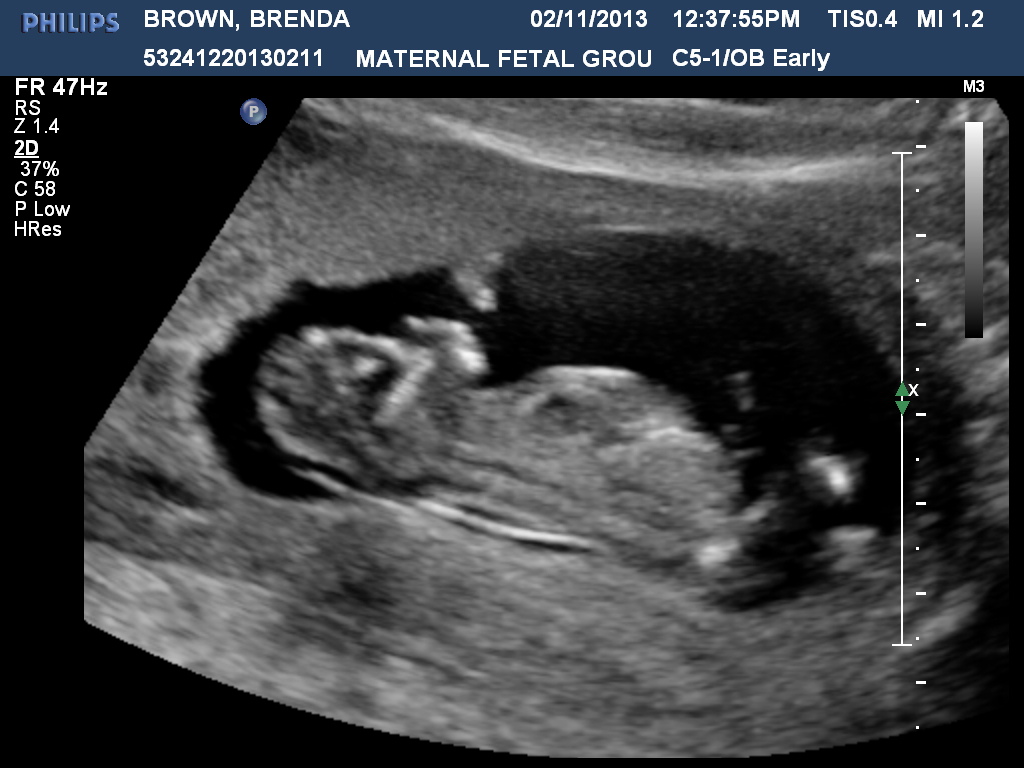

Дефекты кожи у плода узи - фото презентация